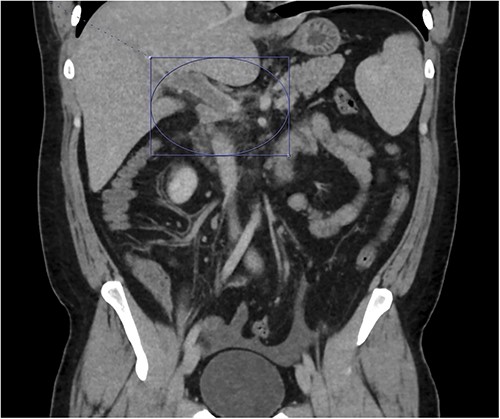

At home, the patient continued to do well and remained free of abdominal pain. He was tolerating a normal diet without emesis and was having normal bowel function. His outpatient CT scan 3 months after discharge demonstrated near resolution of his subocclusive PV and SMV thrombus and attenuated periappendiceal inflammation (Figs 3 and 4). Given the patient’s clinical stability and benign radiographic findings, the patient was scheduled for a laparoscopic appendectomy.

Only a slender portion of thrombus remains in the main portal vein; the previously seen splenic vein thrombosis has largely resolved (not well visualized).